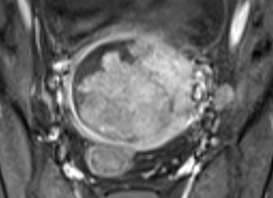

Ca lâm sàng: Fetal fibrosarcoma